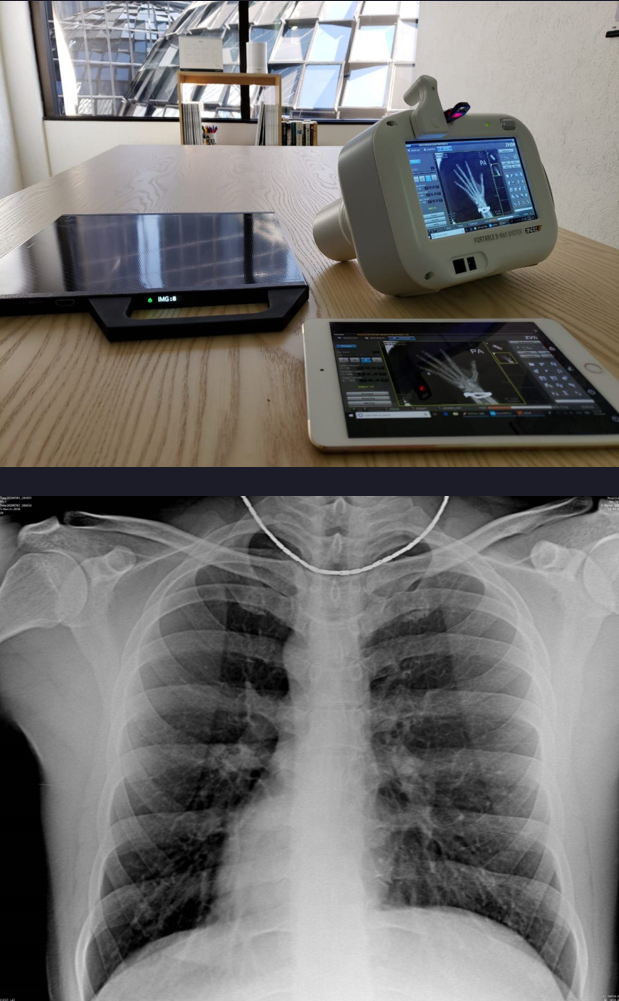

普通数字化X线摄影的第六个趋势:超便携化。

数字化X线摄影技术的超便携化发展趋势发展迅速,近几年移动DR的高速发展应用让便携化X线设备广泛的进入临床,不同于固定数字化X线机的笨重和庞大,便携化X线设备可以超越空间局限,灵活地应用于临床各个科室,检查流程更加高效简单,可以针对不便移动的病人进行随时随地的数字化X线摄影。

在新冠疫情期间,移动数字化X线设备,成为新冠肺炎患者每日影像随访检查的主要设备,在支援全球抗疫中发挥着重要力量。此外,小型便携X光机也在快速发展,随着各种应急能力建设的加快,包括各种自然灾害下的急救与急诊需求,小型轻便化X光机设备在全球得到了快速发展,在应对应急灾害的时候发挥着重要价值。